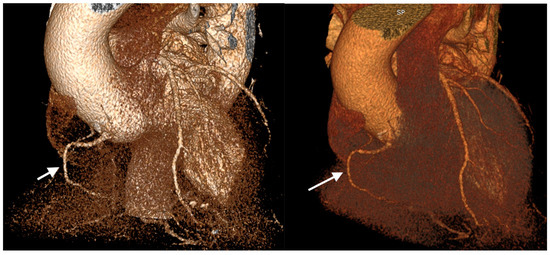

| Coronary artery hypoplasia | 71 | 20.3% | 0.5% |